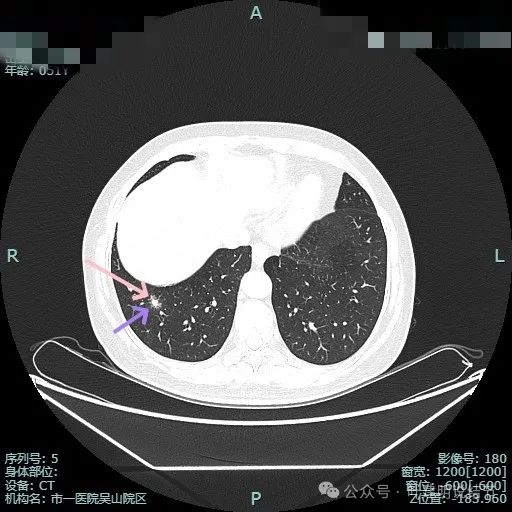

磨玻璃成分有点显得像云雾状,实性成分明显,但乏收缩力。

混合密度,整体轮廓较清,瘤肺边界欠清,整体看没有收缩力。

边缘细毛刺,不太锐利;外围磨玻璃成分,瘤肺界限欠清;中间实性成分明显但缺乏收缩力,实性部分没有明显毛刺征。

灶边有支气管扩张,表面不平,灶内实性成分无收缩力。

血管进入与异常增粗并散开来(在肿瘤性病变中,这种表现是浸润性而且风险大的表现)。

血管进入穿行并异常增粗,磨玻璃成分显得较为散在,缺乏聚拢性。